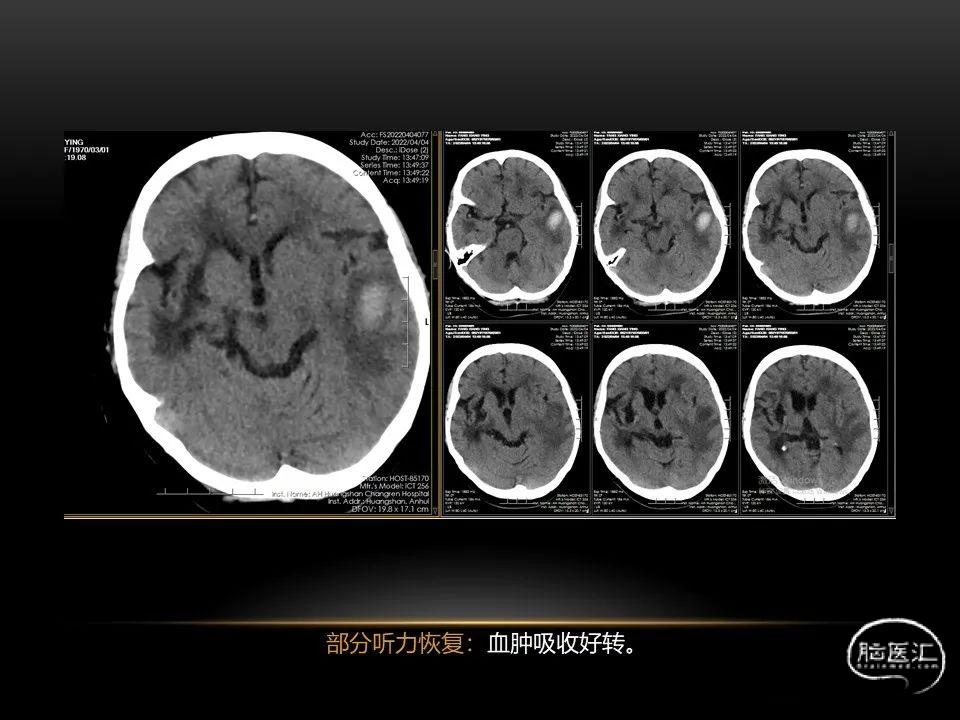

自发性脑出血不仅仅累及内囊后肢才会出现偏瘫及偏身感觉障碍,病变累及大脑脚或辐射冠同样有可能有类似症状和体征。内囊、辐射冠、大脑脚等结构之间是延续的,只是不同区域不同名称而已。定位诊断需要对解剖结构概念清晰,读片准确辨认,灵活掌握。

每位患者的病情都不完全一样,唯有通过不断积累、仔细分辨、细心总结,方能沉着应对,为患者造福。本人水平有限,有空就收集一些手头珍贵资料分析分析,总结总结,回味回味,总会发现很多不懂的,总会有新的收获。望老师和朋友们不吝赐教,给我留言交流心得。